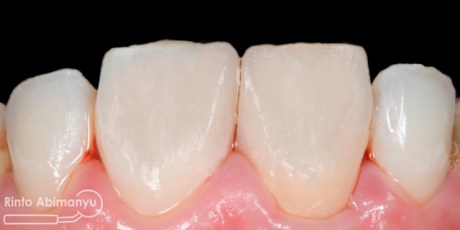

Kemudian dengan bantuan pensil dibuat panduan surface texture, dan mulai dibentuk dengan bur ukuran fine (strip merah) kecepatan rendah… Setelah tekstur selesai kemudian mulai dilakukan pemolesan, saya menggunakan Enhance (Denstply) bentuk point untuk awal dilanjut Soflex Spiral (3M) dan terakhir menggunakan buff…

Alhamdulilah ini hasil akhir dari gigi 11 dan 21…

Gigi 11 dan 21 setelah selesai konturing dan pemolesan